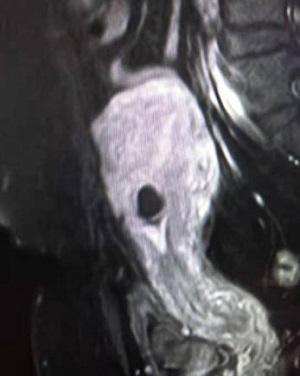

34岁的欧女士来自安仁县,因“停经55天,阴道流血4天,发现切口妊娠2天”于8月22日由门诊以“切口妊娠”收住入院。B超检查提示,剖腹产切口处15x14x11mm孕囊,内见卵黄囊,距离子宫浆膜层4mm,血流丰富。考虑切口妊娠。MRI提示:子宫中段前壁见切口凹陷,有26x15mm大小孕囊附着,附着处16mm肌层变薄,最薄处4mm,子宫前壁与腹壁粘连。诊断:子宫切口妊娠,子宫前壁与腹壁粘连。

超声像                                       MRI影像